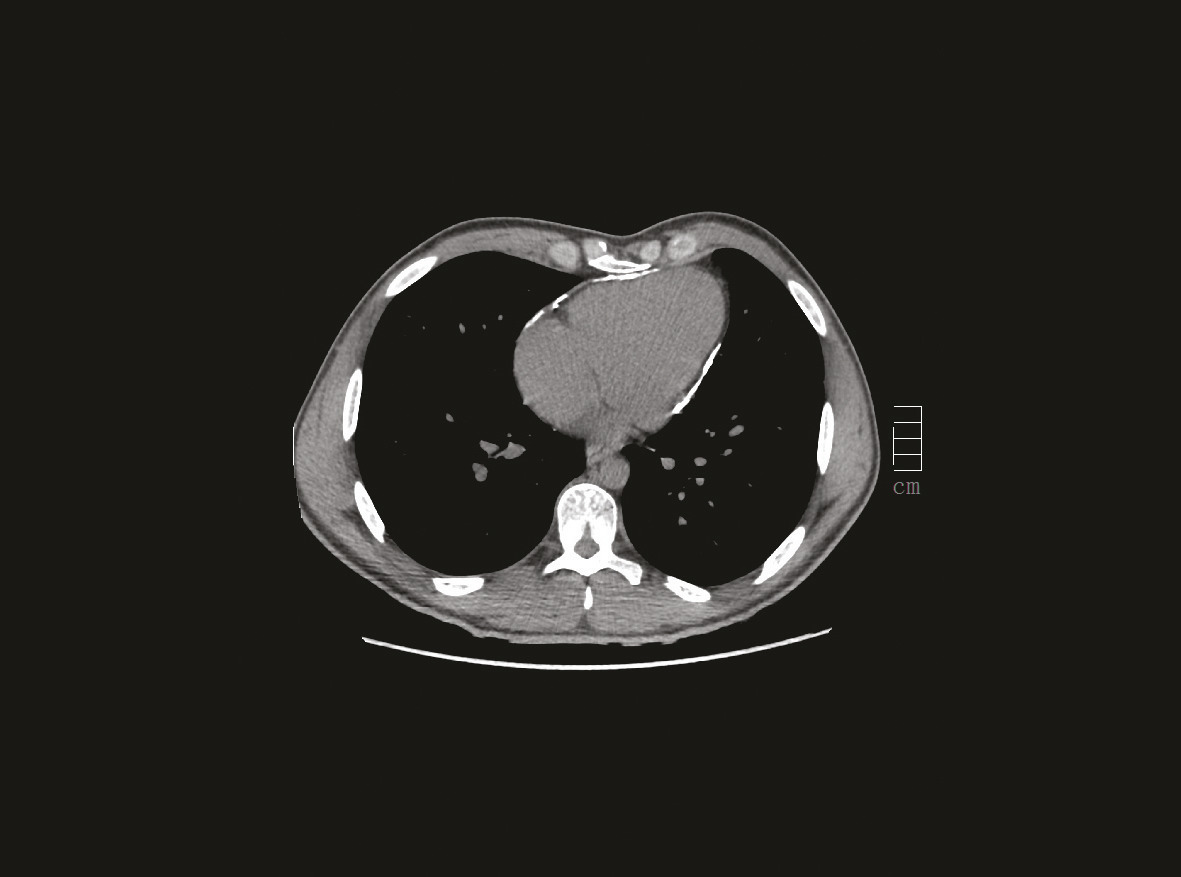

Ce militaire de 25 ans avait des calcifications péricardiques découvertes lors d’un uroscanner (bilan préopératoire de varicocèle). Il avait une fatigabilité à l’effort et une baisse de ses performances sportives. L’échographie transthoracique (ETT) montrait un péricarde épais hyperéchogène d’aspect calcifié et une constriction péricardique. Le scanner (fig. 1 et 2) montrait des calcifications péricardiques circonférentielles sans épaississement ni renforcement péricardique. L’IRM myocardique notait une prise de contraste anormale du péricarde autour du ventricule gauche (VG) avec macrocalcification de la région antéro-latéro-basale, une discrète altération de la FEVG à 51 %, une altération de la fonction systolique du ventricule droit à 28 %, et surtout une dilatation de l’oreillette droite et de la veine cave inférieure, signes de constriction péricardique. L’épreuve d’effort était maximale, négative cliniquement mais positive électriquement avec une majoration des troubles de la repolarisation ; le bilan biologique était normal. Le cathétérisme droit confirmait la constriction. Après décortication chirurgicale du péricarde, les suites opératoires étaient simples avec normalisation en 2 mois de l’épreuve d’effort et de la fonction du VD à l’échographie. Le patient retrouvait ses performances sportives et une surveillance annuelle était instituée.

La péricardite constrictive chronique1-4 est une inflammation chronique rare qui engendre la formation d’une coque rigide autour du cœur limitant sa compliance ; les cavités droites sont plus impactées. Elle est idiopathique, ou survient dans les suites d’une chirurgie cardiaque, de radiothérapie thoracique ou lors d’une maladie de système. Les péricardites tuberculeuses et bactériennes prédominent dans les pays émergents. Le signe initial le plus fréquent est la dyspnée. S’installent ensuite progressivement des signes d’insuffisance cardiaque à prédominance droite. L’ETT, essentielle au diag- nostic, montre un épais- sissement péricardique et/ou des calcifications, une constriction avec une dilatation des cavités droites, un mouvement paradoxal du septum interventriculaire et une dila- tation veineuse ; scanner et IRM thoracique la complètent. Le cathétérisme cardiaque est réalisé si la chirurgie est envisagée : il affirme la diagnostic et permet d’éliminer une cardiopathie restrictive. L’évolution spontanée est toujours sévère. Le traitement est chirurgical (décortication péricardique).